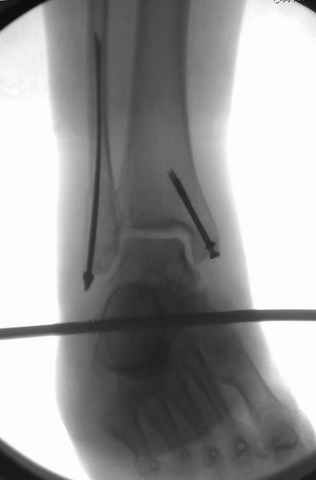

I can't realize why plate fibula separately if anyway external fixator including the foot is planned, i.e. one may insert wires to the talus, calcaneus, lateral malleolus and anywhere else. Plating looks reasonable if only temporary ex-fix is planned, but in the case it will be definitive.

A propos fibular fixation if one is eager to stabilize it separately. In the fracture pattern a way of closed fixation by V-shaped stressed wire (advanced by colleagues from Moscow, prof. Lazarev A.F. et al.) must be excellent. We use indirect closed reduction by the external fixator. Example attached, that fibular fracture is even more suitable for plating but the wire did the job.

Идея хорошая, особенно если короткий и поперечный перелом. Узнал о методе на прошлогодней конференции в Санкт Петербурге, доклад от ЦИТО,

и в доказательство Александр показал на своих снимках оригинальность метода, концепция "сделай сам имплант" из малого разреза и доступность. (при совершенствовании методики и инструментарии, метод может быть применен и в других случаях)